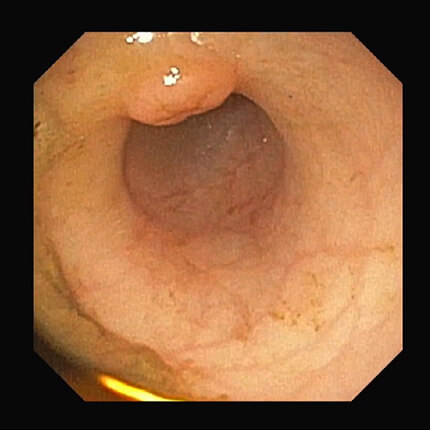

【幽門部】